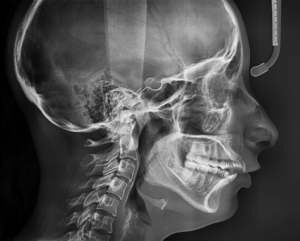

Телерентгенограмма — это метод исследования, при котором используются рентгеновские лучи для создания изображений внутренних структур пациента. Она позволяет визуализировать кости, суставы, органы, сосуды и другие ткани, которые невозможно увидеть невооруженным глазом. Телерентгенограмма представляет собой черно-белое изображение, которое может быть сохранено на пленке или в виде цифрового файла для дальнейшего анализа и интерпретации.

Процедура телерентгенограммы обычно проходит в специально оборудованной рентгеновской комнате или врачебном кабинете. Во время процедуры пациент стоит, сидит или лежит на специальном столе или платформе. Врач или рентгенолаборант располагает рентгеновский аппарат или панель за пациентом и направляет лучи на область тела, которую нужно изучить. Пациент должен быть внимательным и следовать инструкциям медицинского персонала, чтобы получить наилучшие результаты и минимизировать излучение.

Во время процедуры пациенту могут попросить держать дыхание или менять позу, чтобы получить разные ракурсы и изображения. Рентгеновская процедура обычно занимает несколько минут, и результаты могут быть доступны в течение нескольких минут или после дополнительной обработки изображений.